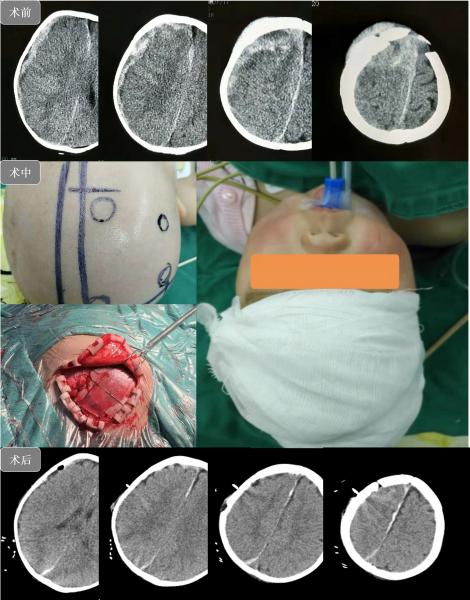

神经外一科宋少裕医师接诊,进行询问病史及详细快速的体格检查。患儿年幼,体重不足10公斤,病程4小时,伤后意识不清,昏迷程度逐渐加重,瞳孔对光反射迟钝,额顶部头皮青紫、肿胀明显(头皮血肿约30ml),前囟门张力高,结合当地医院CT提示患儿前囟门及周围颅骨凹陷骨折,颅内急性硬膜下血肿,约30ml,脑组织挫裂伤,肿胀明显,中线移位,颅内压力极高,一条鲜活的生命随时都有可能到此结束!宋少裕医师立即将患儿病情向科主任向昌华汇报,指示紧急成立抢救小组,务必挽救患儿生命。迅速组织人员进行严格的危重术前讨论,最终确立了开颅清除血肿+颅骨骨折整复的手术方案。

在向昌华主任带领下,手术由万一副主任医师主刀,王钊总住院医师一助,密切合作,历时2小时,在蔡司显微镜辅助下顺利清除颅内血肿及部分坏死失活脑组织,完整保护好重要血管,后将颅骨复位,术后转入儿科重症监护室。在儿科重症医护团队的悉心照料下,曦曦顺利度过了危险期,病情逐渐趋于稳定,转入普通病房开始进一步的康复,目前患儿意识清醒,自主进食,四肢活动自如,已顺利出院!